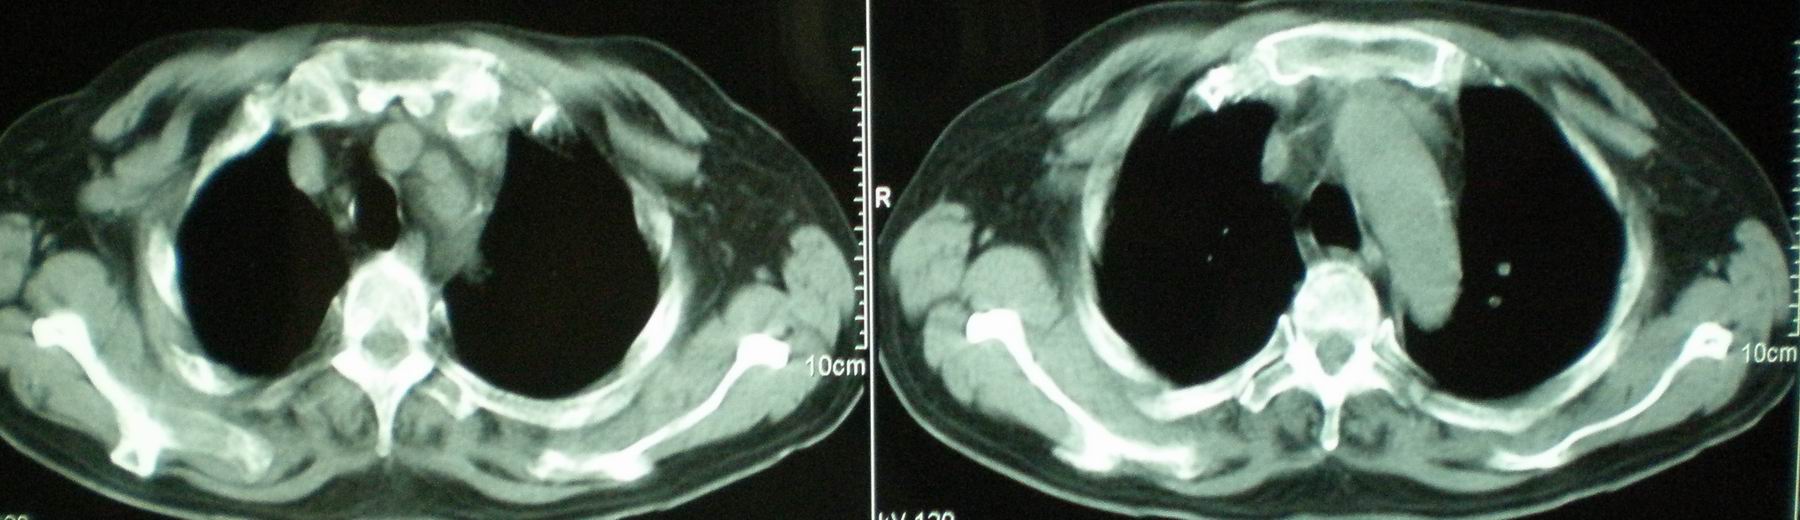

标题: CT16695:男,52岁,复查,有两次对比片及上级医院住院小结 [打印本页]

标题: CT16695:男,52岁,复查,有两次对比片及上级医院住院小结

病人资料:男,52岁,因体癣股癣等皮肤病行激素治疗,因突然大剂量减药而起病,病情危急,9月8日曾在上级医院住院治疗,9月18日复查了ct片,相关检查及住院小结以图片资料上传。

2008年11月18日今天的ct片

2008年9月18日ct片

2008年9月8日ct片: